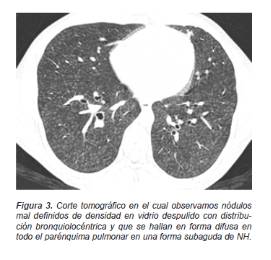

En la fase subaguda predominan las imágenes redondas, pequeñas, mal definidas de distribución difusa, pero con una preferencia broncocéntrica que usualmente se verán sumadas a los cambios agudos (Figura 3).